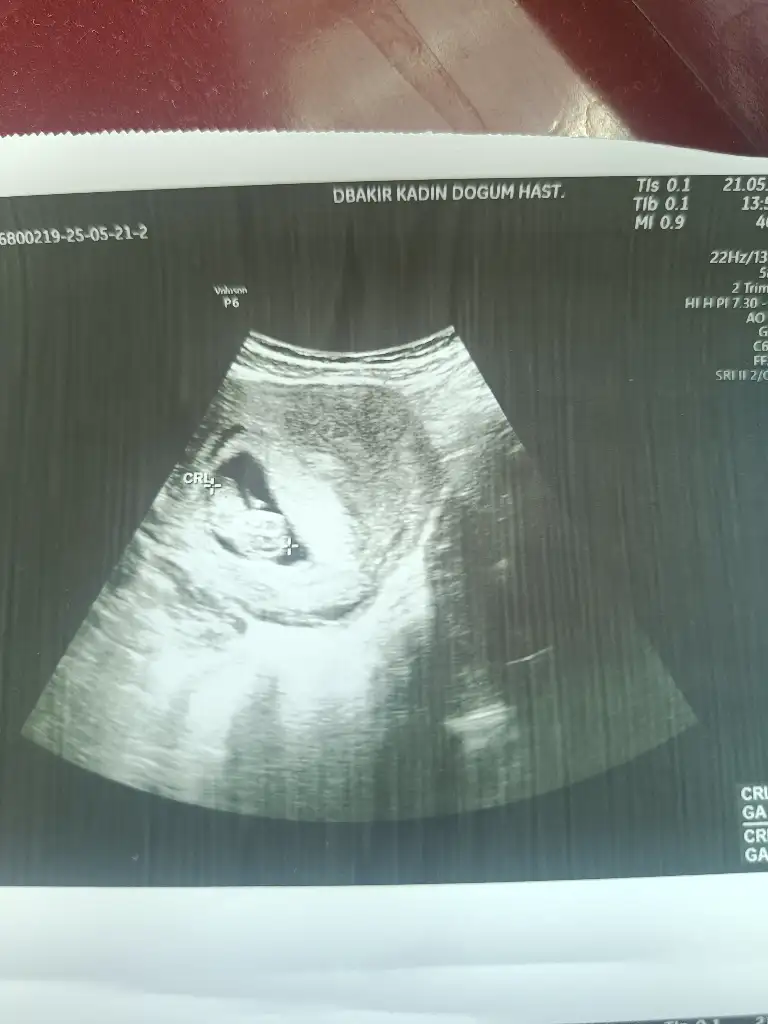

Benimde bakar mısınız?

Eklentiler

• IMG_20250521_140026.webp

28,6 KB · Görüntüleme: 19

• IMG_20250521_140021.webp

24,2 KB · Görüntüleme: 26